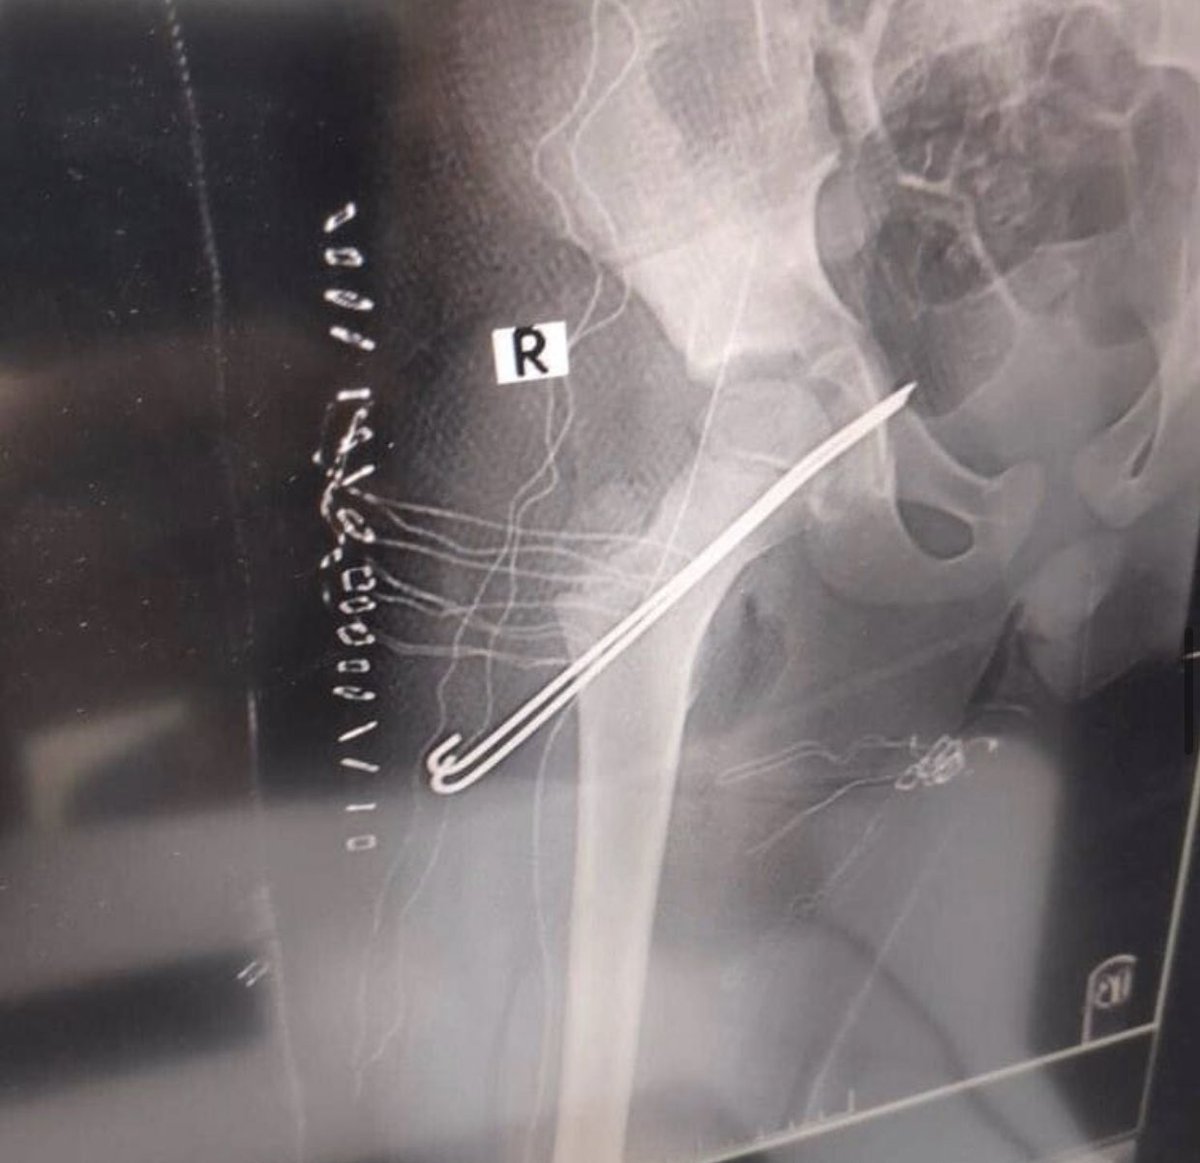

Voilà d& #39;ailleurs comment cet enfant a été traité... Broches, vis et plaques... un coup de visseuse et Hop !

Autres clichés qui tournent à propos du tableau de bord...

Ici, ok c& #39;est un adulte (les cartilages sont fusionnés) et c& #39;est un homme (le bassin est typique)

MAIS ... c& #39;est un accident de moto.

Ici, ok c& #39;est un adulte (les cartilages sont fusionnés) et c& #39;est un homme (le bassin est typique)

MAIS ... c& #39;est un accident de moto.